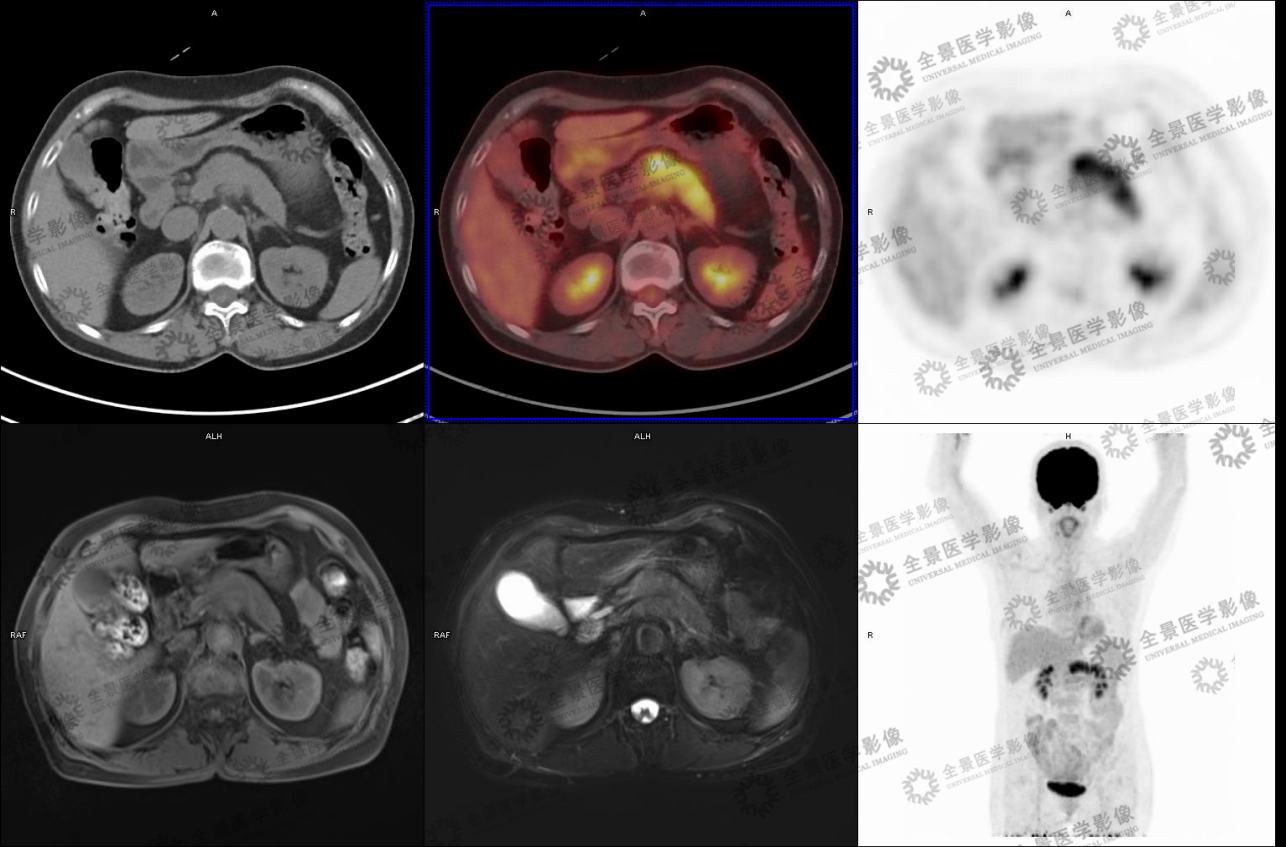

实例一

病史:女70岁 腹部不适,纳差半月,CT:胰腺MT伴小网膜囊淋巴结肿大及血管侵犯。

病灶呈延迟强化,FDG代谢增高,考虑胰腺癌。